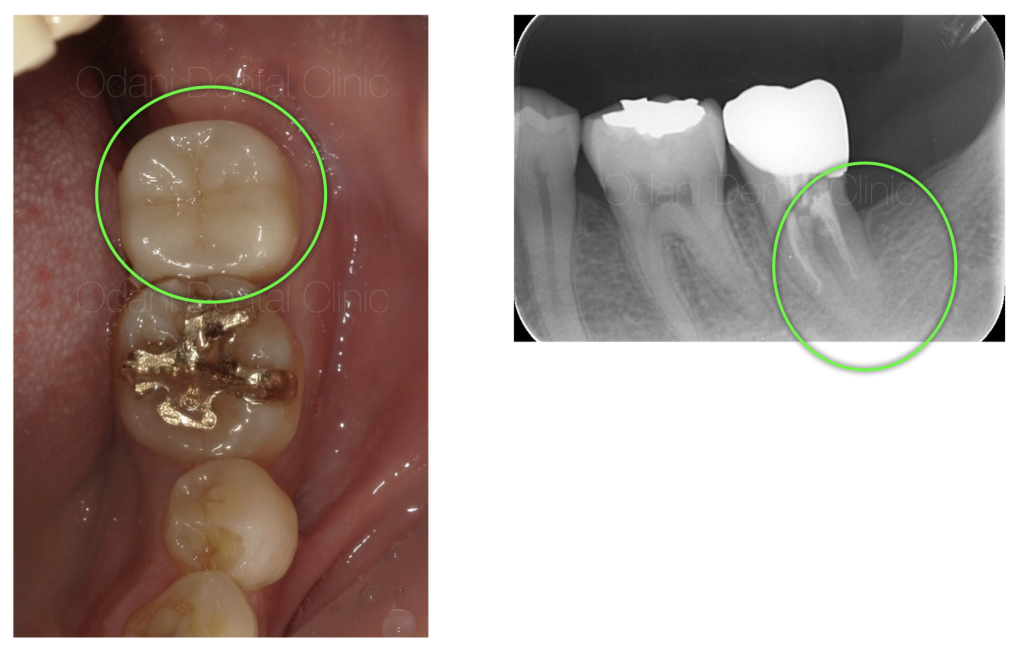

初診時の状態と診断のポイント

診察および画像検査の結果、もともと入っていた詰め物が神経に近く、神経に炎症が起こり、その後神経が壊死してしまったためと考えられます。

CT画像では、歯の根の周囲の骨が大きく吸収していることが確認でき、それに伴い歯ぐきの腫れや、歯周ポケットが7mmと深い状態になっていました。

このまま放置すると、さらに感染が進行し、骨の吸収が拡大すし、歯の保存が困難となる可能性が高い状態でした。

また、感染が歯の周囲に広がった場合、大元の神経とも近く、麻痺や骨髄炎などの重篤な問題につながるリスクも考えられる状況でした。